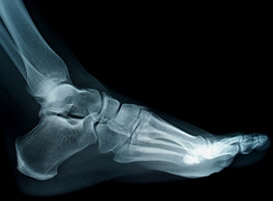

• Hallux valgus/rigidus

• Plantar fasciopathy/heel pain

• Hammer toes

• Posterior heel spurs

• Achilles tendinopathy

• Morton’s neuroma

• Ingrown toenails

• Adult acquired flat foot

• Tendinosis

ANKLE CONDITIONS

• Recurrent ankle sprains

• Ankle impingement syndromes

• Tendon injuries

• Subtalar joint pathology

• Adult acquired flatfoot

• Spring ligament injury

• Ankle arthropathy